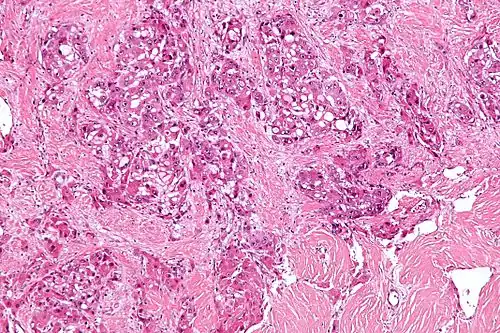

| Micrograph of fibrolamellar hepatocarcinoma showing the characteristic laminated fibrosis between the tumor cells with a low NC ratio. H&E stain. | |

The histopathology of FLC is characterized by laminated fibrous layers, interspersed between the tumor cells. Cytologically, the tumor cells have a low nuclear to cytoplasmic ratio with abundant eosinophilic cytoplasm.[1] Tumors are non-encapsulated, but well circumscribed, when compared to conventional HCC (which typically has an invasive border).